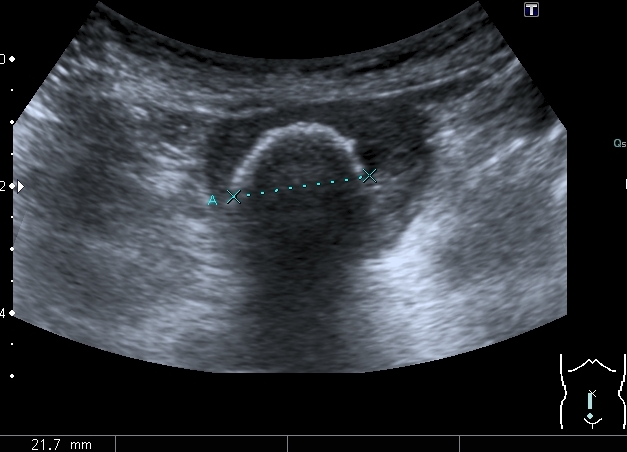

Сокращённый мочевой пузырь

Он же в поперечном скане

Нейрогенный мочевой пузырь (?), МКБ, конкремент мочевого пузыря, двухсторонний мегауретер, конкремент правой почки.

Если честно, и я изначально не совсем понял, где находится конкремент (а это конечно же конкремент), локализованный на урограммах. При первичном исследовании на УЗИ его я не видел (либо он спрятался за тенью конкремента мочевого пузыря, либо я обрадовался редкой находке конкремента такого размера в мочевом пузыре - 2.5 см, и не посмотрел что ниже). Тем не менее при ретроспективном анализе архивированных сонограмм, как мне кажется, он попал в один из сканов, м.б. не совсем чётко.

I20111114160229796.jpg

И всё -же, где конкремент :?: